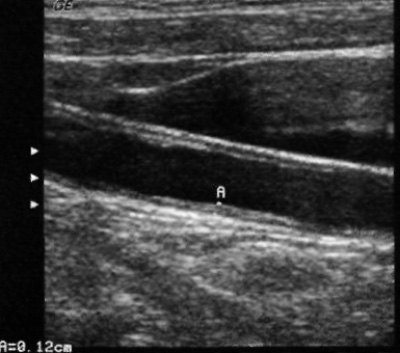

Толщина и характер поражения стенки артерии имеет диагностическую ценность в прогнозе риска развития инсульта, поскольку диффузное увеличение толщины внутренней и средней оболочек сонных артерий сопровождается развитием атеросклероза. Утолщение стенки также является доклиническим маркером сердечно-сосудистых патологий. Измерение толщины комплекса «интима-медиа» проводят путем определения средней или максимальной толщины по всей длине сосуда. В норме толщина стенки сосуда составляет 0,6-1,0 мм (фото 10).

Фото 10. Утолщение стенки артерии. Курсорами обозначено утолщение стенки внутренней и средней оболочек общей сонной артерии